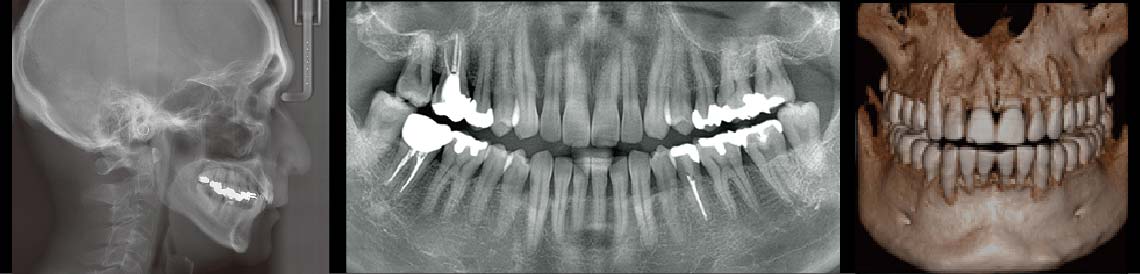

CTスキャナーとは「コンピューター断層撮影装置」のこと。通常のレントゲン写真が2次元のみの撮影なのに対し、3次元(水平・垂直・奥行)で撮影できるため見たい断面を自在に表示でき、3D画像での診断が可能で、正確な治療のガイドラインになります。

歯科医療に求められること、それは「精密治療」アルファ歯科プラスでは、高性能3次元CT撮影機を導入しています。 そして、歯科医師・歯科衛生士すべてのスタッフが拡大鏡を装着。さらにマイクロスコープ歯科用顕微鏡を導入することにより精密の極み「超精密」治療も実現可能となります。マイクロスコープ(歯科用顕微鏡)を使用することにより、最大20倍まで拡大視の元、超精密治療が可能となります。